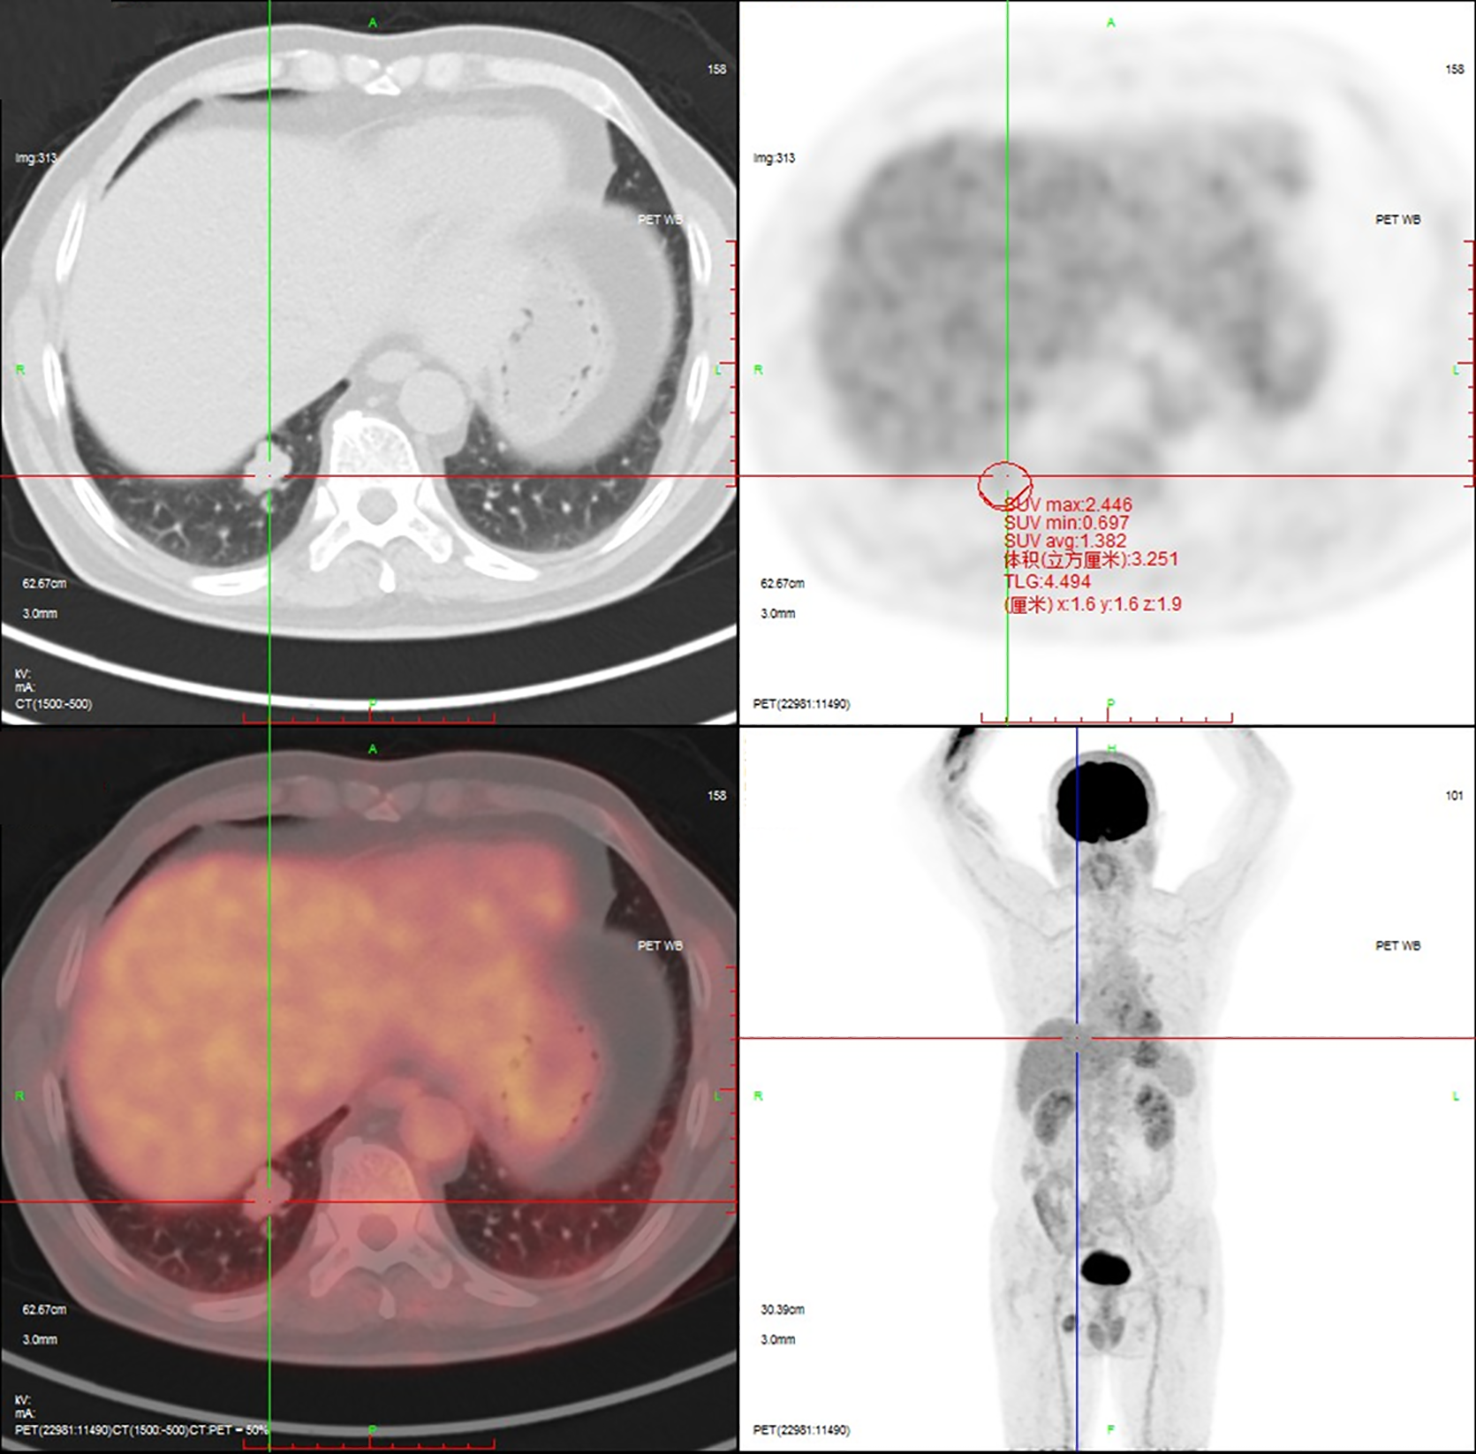

18F-Fluorodeoxyglucose Positron Emission Tomography-Computed Tomography (18F-FDG PET-CT) imaging demonstrated mild metabolic activity within the nodule, exhibiting a maximum standardized uptake value (SUVmax) of 2.4 (Figure 2). The imaging findings were indeterminate between granulomatous inflammation and neoplastic lesions, necessitating histopathological confirmation via biopsy. Whole-body bone scintigraphy using emission computed tomography (ECT) revealed no evidence of pathological skeletal lesions (Figure 3). All laboratory parameters were within normal limits: negative for lung cancer biomarkers (CEA, NSE, CYFRA 21-1, ProGRP) and unremarkable hematological/inflammatory profiles (WBC, neutrophils, CRP, ESR).

Figure 2

18F-FDG PET-CT demonstrates mild metabolic activity within the nodule, exhibiting a SUVmax of 2.4.